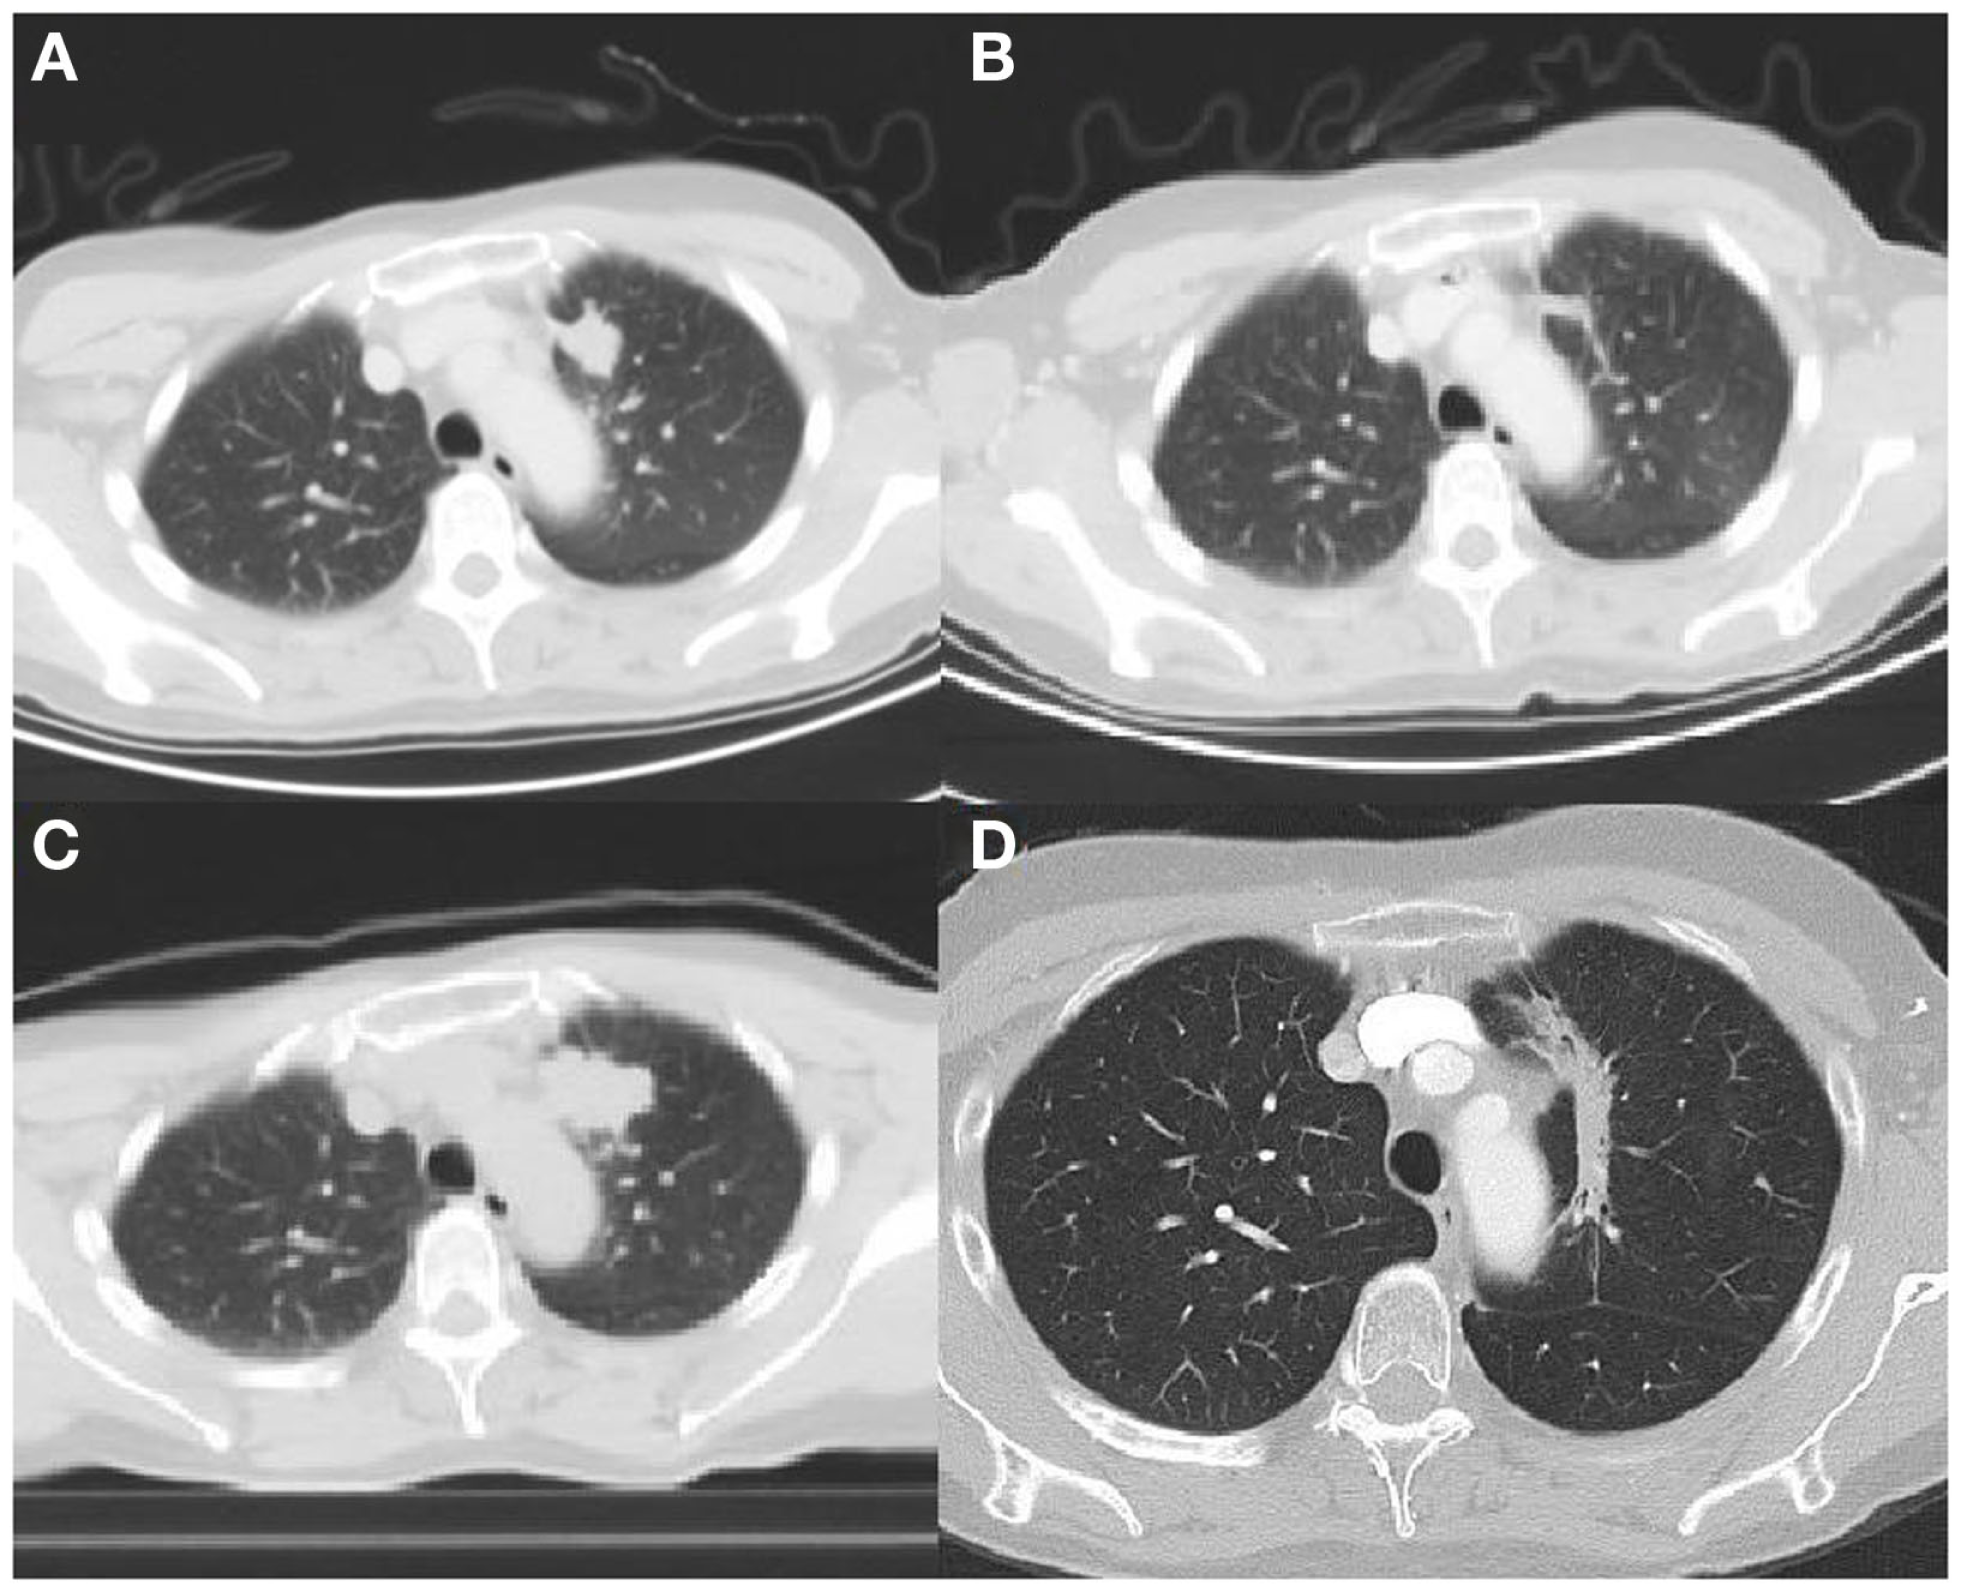

The second case concerns a 66 years old male ex-smoker (6 PY during adolescence). In May 2010, an EGFR mutation (L858R c.2573T > G) positive adenocarcinoma of the right lower lobe of the lung with metastasis in the contra-lateral lung was diagnosed (Figure 2A). In June 2010, afatinib, a irreversible EGFR-HER2-inhibitor, was started in a clinical trial (Gilotrif® in BIBW 2992 trial). The patient experienced partial response (Figure 2B) until July 2012, 26 months after initial diagnosis. At that point, local progression was seen at the site of the primary tumor in the right upper lobe, and no distant metastases (Figure 2C). There was a multidisciplinary consensus to start local hypofractionated radiotherapy (20 Gy × 3 Gy) and stop TKI during this treatment. After completion of the radiotherapy gefitinib was started. A significant decrease of the tumor was seen (Figure 2D). One year later, in June 2013, a new pleural effusion was seen and proven to be metastatic disease. A switch to standard chemotherapy was initiated in October 2013 after pleurodesis. We note stable disease until April 2014. At that point, erlotinib was started because of progressive disease. Four months later, brain metastasis were diagnosed which where treated with whole brain radiotherapy (5 Gy × 4 Gy). Erlotinib was continued afterwards. Until October 2014, we note stable disease.

Figure 2

(A) Tumor lower right lobe on diagnosis (CT scan). (B) Partial response 22 months after start TKI (CT scan). (C) Local progression 26 months after diagnosis (CT scan). (D) Partial response 9 months after local radiotherapy (CT scan).

The third case concerns a 59 years old female never smoker. In January 2009, she was diagnosed with an adenocarcinoma of the lung (left upper lobe) with bone and liver metastasis (Figure 3A). The tumor was EGFR mutation positive, with a deletion found on exon 19. In February, erlotinib was started in a clinical trial (FIELT study) with near complete remission (Figure 3B). 18F-FDG PET-CT showed no distant metastases. After 34 months, the FIELT study was closed. At that point, in December 2011, we made a switch to gefitinib because erlotinib was not yet reimbursed in first-line treatment. In May 2012, 6 months after switch to gefitinib progression of the tumor in the left upper lobe was seen (Figure 3C) and local stereotactic body radiotherapy was given (8 Gy × 7.5 Gy). Gefinitib was stopped during radiotherapy but restarted afterwards. A significant decrease of the tumor was seen (Figure 3D).

Figure 3

(A) Tumor left upper lobe on diagnosis (18F-FDG PET-CT scan). (B) Near complete response 32 months after start TKI (18F-FDG PET-CT scan). (C) Local progression 40 months after diagnosis (18F-FDG PET-CT scan). (D) Partial response 8 months after local radiotherapy (CT scan).

Until October 2014, we note stable disease, 27 months after local therapy.